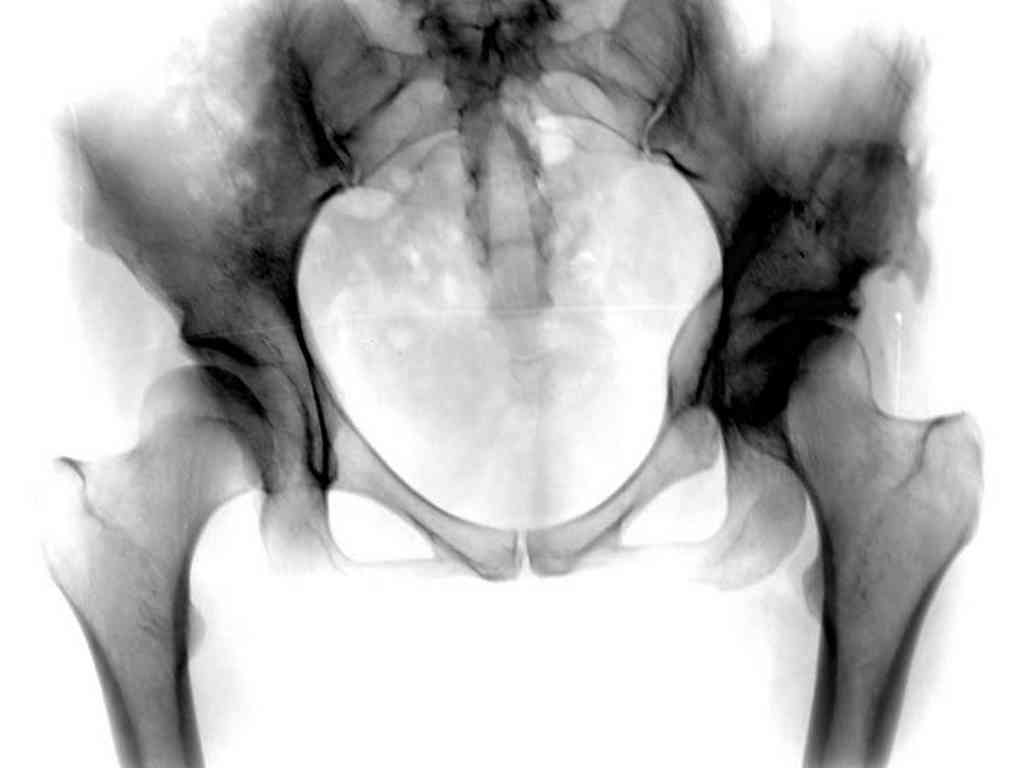

Типичная концовка проигнорированного диспластического состояния сустава. Дисплазия тазобедренного сустава часто встречающаяся патология у жителей Центральной Азии вследствие тугого пеленания в детстве. Традиционно ребенок находится в течение дня в так называемой кроватке "бешик", удобной в быту, но она впоследствии приводит к недоразвитию тазобедренного сустава.

У женщин болезнь клинически проявляется после беременности болями в суставе. Но во время беременности из-за невозможности рентген обследования проблема игнорируется, и упускается время. После беременности симптомы исчезают, и проявляются во время следующей беременности или после увеличения веса.

Это первые признаки начала деструкции сустава, и возможно, аналгетики помогут для купирования болей, но в течение очень короткого времени от сустава ничего не останется, и в дальнейшем останется только артропластика.

При более сохранном суставе от дальнейшего разрушения можно было бы сохранить только периориентацией нагрузки на сустав - Периацетабулярной Остеотомией .

Данный сустав в начальной стадии разрушения, но все-таки я бы сделал обзорный таз и отдельные снимки сустава в 30 градусной абдукции и аддукции. Также снимки с внутренней и наружной ротацией для оценки состояния головки бедра.